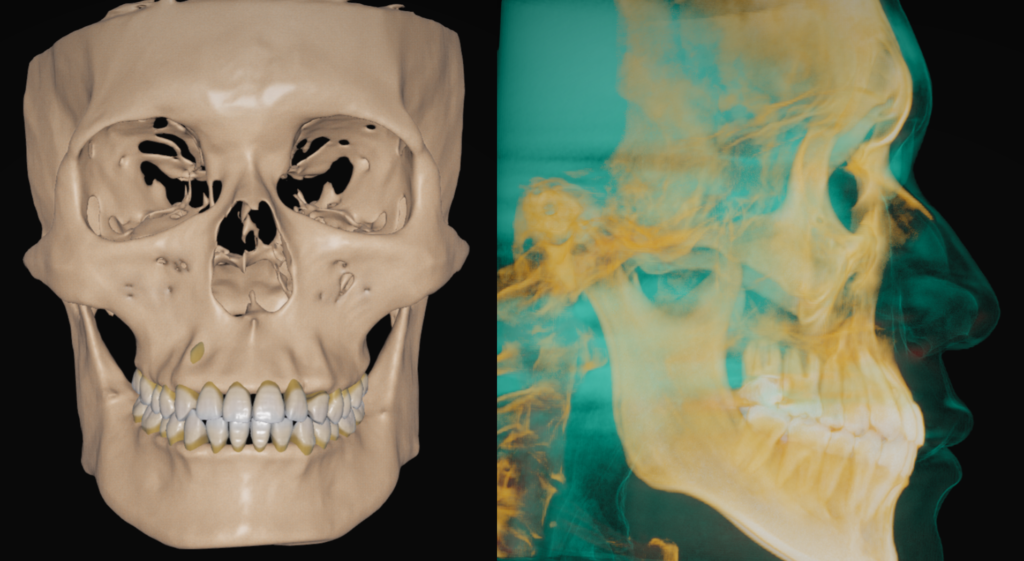

①CT

歯を動かす際には、歯を支える歯槽骨の状況を見る必要があります。

子供の方でも大人の方でも、歯が骨の中に埋まっている埋伏歯の位置関係を見ることもできます。

歯と骨の総合的な情報を得るためにCTは必須になります。

②フェイススキャン

上記のCTデータを組み合わせることで、皮膚と骨の位置関係をより詳細に知ることができます。

デジタル上で歯型を取ります。スキャンデータをCTと合わせることで、口腔内の状態を正確に再現できます。

抜歯したスペースや歯列拡大などを行った場合、どういう結果になるかなど主に治療計画を立てる際に必要になります。